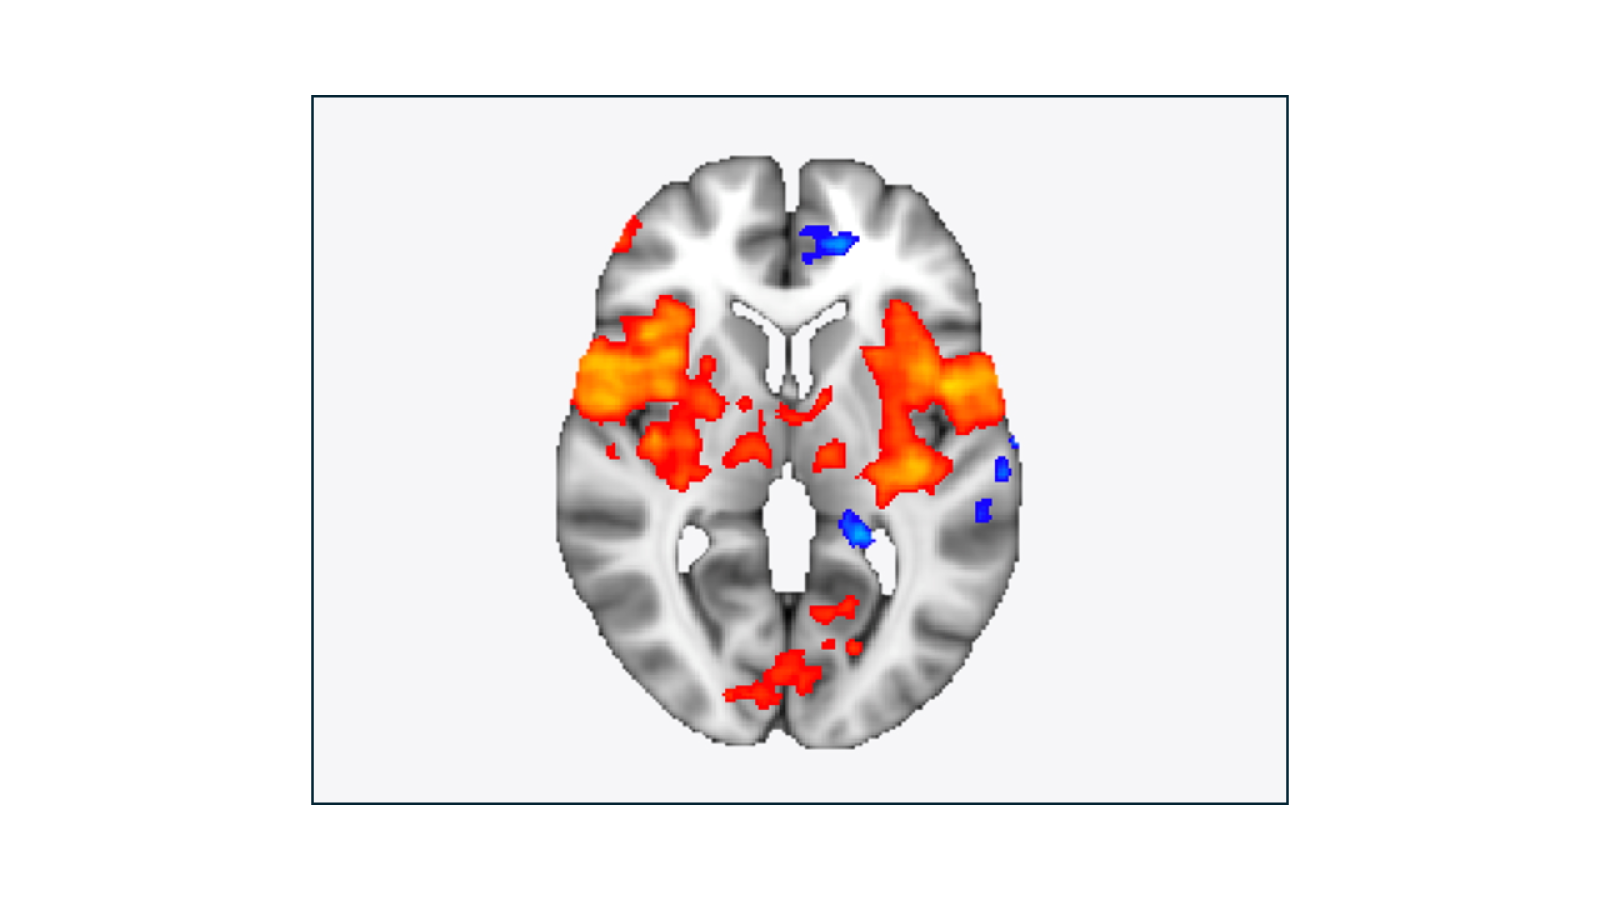

The Brain in Pain - An example of how the brain responds when we feel physical pain, in this case, people were experiencing heat pain on their leg while they were in an MRI scanner.